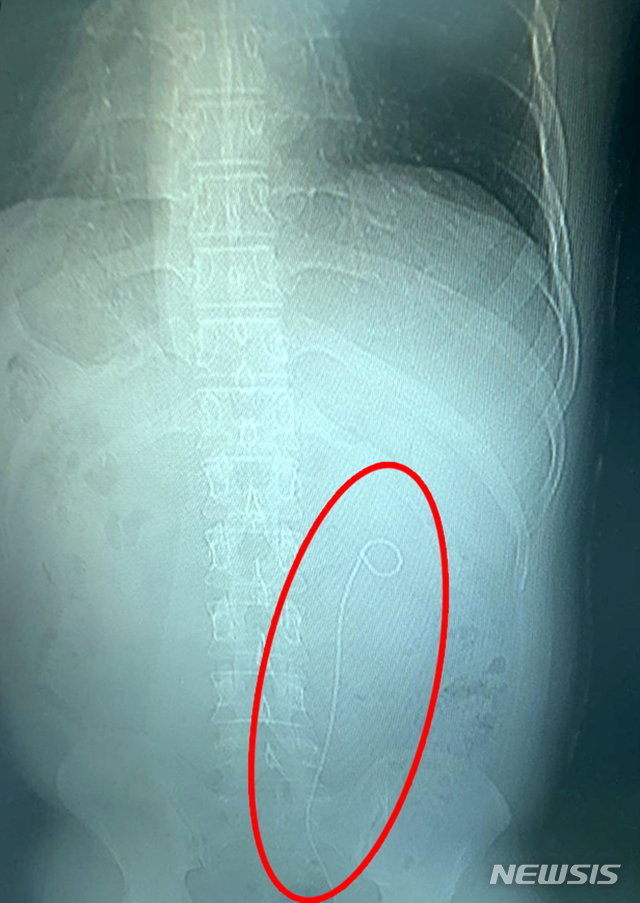

【광주=뉴시스】구용희 기자 = 30대 결석 환자 몸속에서 발견된 수술기구. 이 환자는 지난 2015년 광주 모 대학병원에서 결석 제거 수술을 받았다. 이후 지난 10월 같은 병원에서 진단서를 발급받기 위해 영상검사를 받는 과정에 당시 수술에 사용했던 기구가 몸속에 남아 있다는 사실을 발견했다. 2018.12.18. (사진 = 해당 30대 환자 제공)persevere9@newsis.com

영상 촬영 결과 자신의 몸속에서 28㎝가량의 수술용 기구가 발견됐기 때문이다.

대학병원 측 관계자는 "B 씨의 몸속에서 발견된 기구는 당시 수술에 사용됐던 일종의 부목이다. 이 기구는 결석 제거를 위한 지지대 역할을 했다"고 설명했다.

이어 "수술 뒤 환자 상태에 따라 1∼2개월 또는 2∼3개월 이후 제거해야 하는 기구이다. 최대 6개월까지 제거하지 않아도 된다. 이 기간 내 제거하지 않은 과실이 있다. 병원에서도 일정 부문 책임질 방침이다"고 말했다.